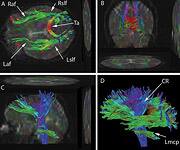

Traumatic brain injury (TBI) is often referred to as the "signature wound" of both the Iraq and Afghanistan wars. Traumatic brain injury occurs when a sudden trauma to the head disrupts brain function. In both these wars, however, even close proximity to the force of an explosion can be just as devastating. Most of the reported traumatic brain injury among Operation Enduring Freedom and Operation Iraqi Freedom veterans has been traced to improvised explosive devices, or IEDs. "Traumatic brain injury can be caused by a direct impact, or by acceleration alone," explains Dr. Mark L. Gordon, interventional endocrinologist and traumatic brain injury treatment specialist at Millennium Health Centers in Los Angeles. "Brain trauma also causes secondary injury, which takes place in the minutes and days following the injury," he adds. "These processes include alterations in cerebral blood flow and increased pressure within the skull, contributing substantially to damage from the initial injury." Gordon says traumatic brain injury can cause a host of physical, cognitive, emotional, and behavioral effects, some of which can be difficult to detect. Symptoms can appear immediately or weeks to years following the injury. "Insidious traumatic brain injury can be difficult to detect," Gordon says. "Localized damage to the frontal and occipital lobes occurs when the brain collides with the skull. Increasingly, we are discovering that traumatic brain injury is also a causative factor for accelerated hormonal deficiencies." These deficiencies, says Gordon, can cause a host of psychological, physiological, and physical manifestations, including depression, outbursts of anger, anxiety, mood swings, memory loss, inability to concentrate, learning disabilities, sleep deprivation, increased risk for heart attacks, strokes, high blood pressure, diabetes, loss of libido, menstrual irregularities, premature menopause, obesity, loss of lean body mass, muscular weakness, and a number of other medically documented conditions. What's more, Gordon points out that veterans suffering from these forms of psychological damage due to traumatic brain injury are frequently misdiagnosed and have their injury erroneously downgraded to post-traumatic stress disorder (PTSD). Moreover, especially in mild traumatic brain injury cases, symptoms at the initial time of injury may go unrecognized or unnoticed, but patients will still develop hormone deficiencies. Unfortunately, the government is slow to accept the link between traumatic brain injury and hormonal deficiencies. Dr. Gordon's Epiphany

By sheer serendipity, many years ago Dr. Gordon provided care for a young man with a history of numerous sports-related head injuries, whose parents were themselves patients at the clinic. The young man's symptoms long outlasted the immediate effects of his acute injury and included loss of concentration, memory, mental energy, focus, and physical well-being, often accompanied by loss of lean muscle mass and an increase in body fat. The parents, familiar with the effects of hormonal imbalances, naturally assumed that their son's problems might reflect an endocrine problem of his own. And indeed, many of his symptoms resembled those of adult patients with so-called hypopituitarism, or loss of pituitary gland function. The pituitary gland is located at the base of the brain and is sometimes called the "master" gland of the endocrine system, because it controls the functions of the other hormone- secreting glands. Gordon, who is nothing if not intellectually curious, hit the books. What he found was startling and life-changing, for himself as a clinician, for his young patient, and now for scores of additional victims of traumatic brain injury. Symptoms of Traumatic Brain Injury Mimic Pituitary DysfunctionDr. Gordon found a wealth of published literature suggesting that traumatic brain injury causes pituitary dysfunction, confirming his initial hunch.1 Although the figures vary between studies, at least 50% (and up to 76%) of traumatic brain injury victims show some loss of pituitary hormone function immediately after the brain injury.2-4 In general, the more severe the original brain injury, the more profound the hormonal deficits, although hormone deficiency or insufficiency (levels in the low "normal" range) are seen even in patients with mild traumatic brain injury.5-9 And while about 58% of patients recover their normal pituitary function within one year of their head injury, a shocking 52% develop new pituitary hormone deficiencies after one year. 10,11 Those deficits include reductions in many different pituitary hormones, including those that regulate the thyroid gland, the adrenal glands (that produce cortisol, DHEA, and other vital hormones), the gonads (where estrogen and testosterone are produced), and growth hormone.3,4,12,13 The severity of the hormone deficiencies correlates strongly with the kinds of symptoms Dr. Gordon was seeing in his patient. For example, patients with growth hormone deficiency or insufficiency had significantly worse disability rating scores, greater rates of depression, worse quality of life, lower energy, greater fatigue, and poorer emotional well-being, compared to brain injury patients with normal hormonal levels.14,15 Dr. Gordon's hunch was borne out: patients with traumatic brain injury often have pituitary hormone deficiencies or insufficiencies, especially in growth hormone. And those defects are closely associated with the persistent neurological, psychological, and emotional deficits that are so tragically common in survivors of traumatic brain injury. And where are you most likely to find a high concentration of survivors of traumatic brain injury? The United States military.

Growth Hormone: A Critical PlayerGrowth hormone is the most common hormone deficiency or insufficiency in patients with traumatic brain injury at any level of severity.16-19 Deficiencies in this hormone are especially marked in patients with moderate to severe traumatic brain injury.20 Brain-injured patients with growth hormone deficiency experience rapid weight gain and have substantially lower levels of other hormones as well.17,19 Low growth hormone levels are also associated with excessive anxiety and depression and poor physical health and quality of life.15,21 Finally, brain-injured patients with growth hormone deficiency show greater deficits in attention, executive functioning, memory, and emotion than those with normal growth hormone levels.22 Growth hormone is an intriguing hormone, and we are learning more about it each year. In children, it is responsible for regulating linear growth, ultimately determining adult height and body proportions. But growth hormone has many other remarkable functions throughout the body and into adulthood. It is neuroprotective, increasing survival of damaged nerve cells and promoting regeneration of nerve tissue.23-25 Growth hormone also increases the number of receptors for other hormones in tissues throughout the body; this has the effect of increasing the body's sensitivity to those hormones' actions, helping to overcome the effects of their deficiencies.26-29 Like all hormones, growth hormone acts by binding to specific cell-surface receptors. Receptors for growth hormone are found throughout the brain, and they are especially densely distributed in brain regions responsible for learning and memory.30,31 That may explain why declining growth hormone levels are associated with poorer cognitive function. Growth hormone levels fall with age and are especially low in Alzheimer's disease.32-36 As Dr. Gordon points out, it is therefore not surprising that traumatic brain injury patients often show symptoms identical to the cognitive decline and memory loss we see with aging and Alzheimer's disease. In essence, a brain-injured patient with low growth hormone levels undergoes accelerated cognitive aging. Hope for Traumatic Brain Injury Patients at Millennium Health Centers